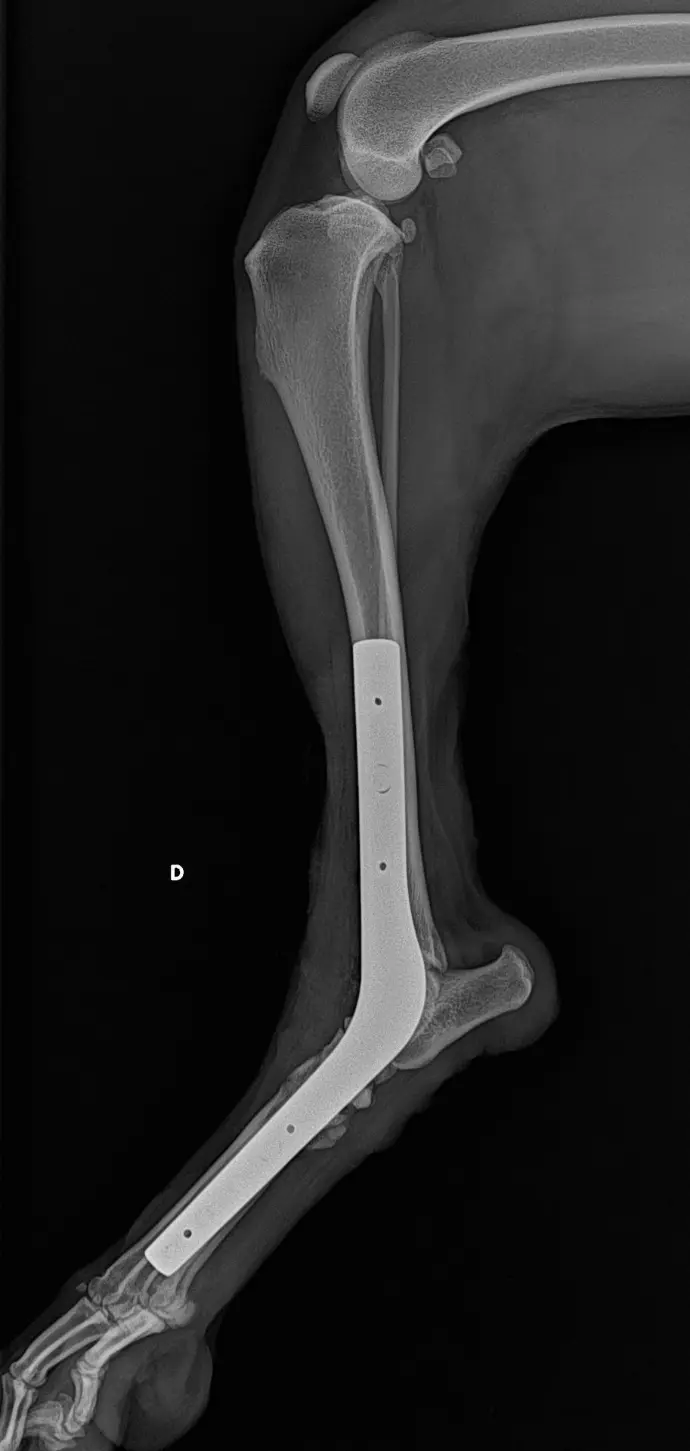

Arthrodèse

- Repos strict pendant 6 semaines : garder votre animal en cage.

- Pas de saut ni de jeux, courtes sorties en laisse uniquement pour les besoins.

- Ne pas laisser votre animal lécher le bandage ou les sutures, maintenir la collerette jusqu’au retrait des points si nécessaire.

- Contrôle dans 12-14 jours : retrait du bandage, contrôle de la cicatrisation, retrait des points.

- Contrôle radiographique dans 4 à 6 semaines et dans 2 à 3 mois selon l’évolution de la fusion osseuse.